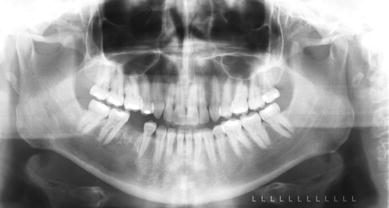

A 42-year-old Caucasian female presented with extreme pain of the right mandible and paresthesia of her right lower lip from the commissure to the midline. The patient reported that sudden severe pain began 4 months earlier in the right mandible. Consultation with a private dentist for the pain resulted in the initiation of endodontic therapy for tooth #30. Subsequent to the completion of root canal treatment on tooth #30, the pain increased and the paresthesia began. Both the pain and paresthesia were non-responsive to a short course of steroids and antibiotics. Tooth #30 was extracted 1 month prior to presentation. Following the extraction, the pain and paresthesia worsened and a “swishing” sound developed in her right ear. Evaluation by otolaryngology was negative. Intraoral and extraoral examinations were unremarkable except for the right lower lip paresthesia. Panoramic (Fig. 1), occlusal (Fig. 2) and periapical radiographs (Fig. 3) were taken at the time of presentation.

Fig. 1

Panoramic radiograph